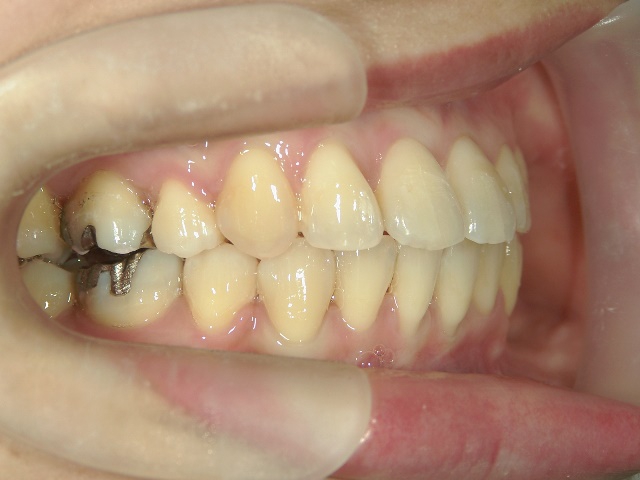

矯正歯科(全顎ワイヤー矯正)治療後

矯正歯科 治療後